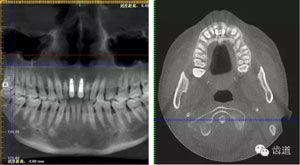

術(shù)后CT

戴牙后CT

本病例為前牙外傷致根折,牙周無(wú)明顯炎癥,唇側(cè)骨板厚度大于1mm且根方骨量充足,適合即刻種植。術(shù)前簡(jiǎn)易導(dǎo)板的制作以及術(shù)中牙周探針精確的測(cè)量,保證了種植體的三維位置及軸向均按標(biāo)準(zhǔn)的即刻種植手術(shù)進(jìn)行。術(shù)后參考拔除牙齒的頸部形態(tài)制作個(gè)性化愈合基臺(tái),實(shí)現(xiàn)了對(duì)牙齦塑型的早期干預(yù),打破了傳統(tǒng)二期牙齦成型的做法,所成型的牙齦袖口與之前的天然牙相似,有利于維持牙齦形態(tài)的穩(wěn)定和美觀。